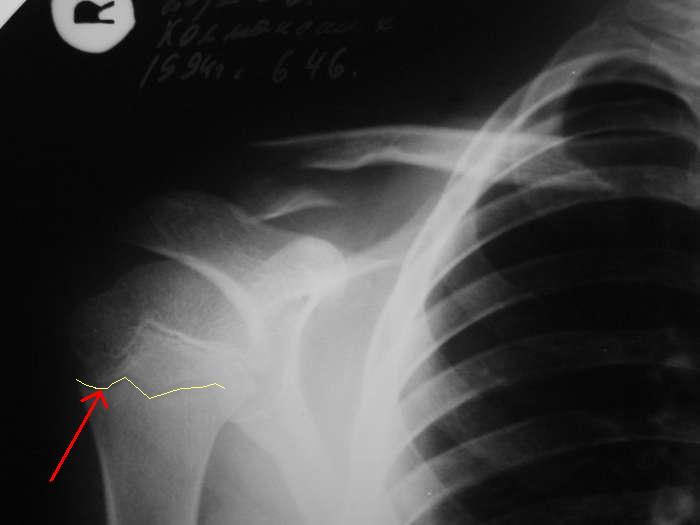

Александр, простите за настойчивость, на картинке я указал смутившую меня тень ... это вариант зоны роста?